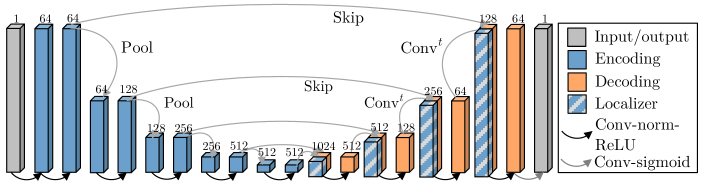

We use a 3D U-Net [12] with blocks in the contracting and expanding paths. Each block consists of two sets of convolution with ReLU activations, followed by max pooling (contraction path) or transpose convolution (expansion path), as illustrated in Fig. 2. We augment the images using random affine transforms, flips, whole-image brightness shifts, contrast changes, random noise, and elastic deformations, using TorchIO [11]. We simulate the effects of maternal normoxia and hyperoxia with a constant intensity shift in the placenta.